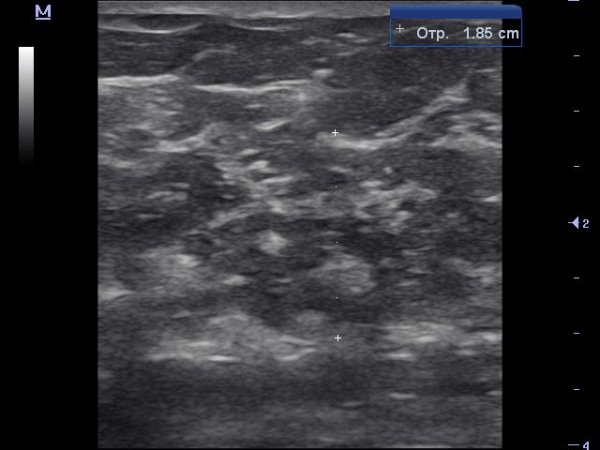

Темерь покажу какая должна быть структура железы в постменопаузальном периоде в норме, кстати кинопетля снята у этой же женщины с участка в нижне-внутреннем квадранте.

Вот пример когда паренхима железы полностью замещена жировой и фиброзной тканью, что характерно для постменопаузального типа строения молочной железы.

В н/н квадранте:

В н/в частично как предпоследняя согорамма и частично как на последнем видео.